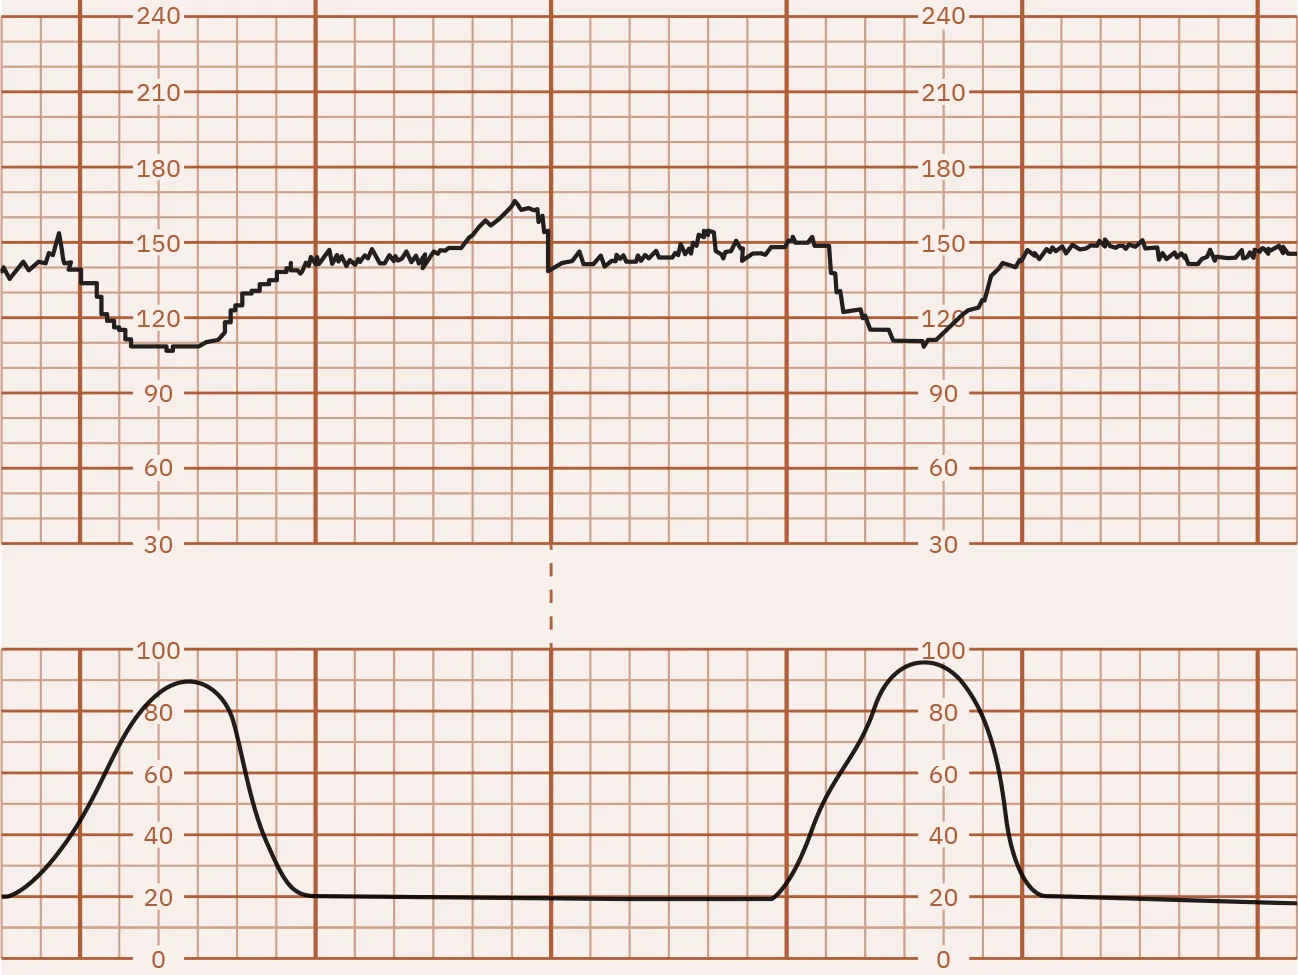

Late Decelerations

Decelerations in the FHR below the baseline that start during a contraction and continue after completion of the contraction are called late decelerations. Figure 16.12 illustrates late FHR decelerations. Late decelerations are nonreassuring and almost always indicate fetal hypoxia. They are associated with uteroplacental insufficiency, a lack of oxygenated blood coming from the uterus to the placenta to the fetus. During a contraction, the decrease in oxygen to the fetus causes a deceleration that begins late in the contraction. The nadir, or lowest point, of the deceleration is after the peak of the contraction. Another common cause of late decelerations is tachysystole (contractions occurring too frequently or lasting longer than 2 minutes), often seen with the use of oxytocin (Pitocin). Spinal or epidural anesthesia causes hypotension leading to hypoperfusion to the placenta, producing late decelerations. Other causes of late decelerations are hypertension, postmature placenta, placental abruption, and anemia. Late decelerations, like early decelerations, are often repetitive, forming a pattern.

Fetal heart rate reading indicating late decelerations.

Figure 16.12 Monitor Tracing Showing Late Decelerations of the FHR The FHR decreases during the contraction and does not return to baseline until after the contraction ends. These are defined as late decelerations. (attribution: Copyright Rice University, OpenStax, under CC BY 4.0 license)